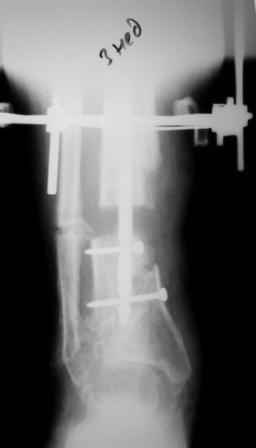

Коллеги!Позвольте продолжить обсуждение темы «ложный сустав левой голени.» Больной К 45 лет, начало см. http://www.weborto.net/forum/1228422607/ И рассказать о результатах проделанной работы. Остановились на следующей тактике 1) Наложить Аппарат Илизарова. В аппарате восстановить оси трех смещенных относительно друг-друга фрагментов большеберцовой кости. Устранить вальгусную деформацию дистального отдела большеберцовой кости. Что и было выполнено. - Была выполнена репозиция в аппарате (рис1) 2) После репозиции более очевидна стала проблема дефекта кости в верхней трети голени, два фрагмента свободно лежат. Остановились на варианте перехода на интрамедуллярный синтез стержнем с покрытием костный цемент+ванкомимцин и замещении дефекта с помощью транспорта фрагмента (рис 2) 3) Третьим этапом наложили модуль на промежуточный фрагмент.(рис 3) И начали его транспорт на стержне в проксимальном направлении. (рис 3 а) Надеемся что «вырастет» регенерат в дистальном отделе, а в проксимальном отделе фрагмент «упрется» и прирастет. Хочу сказать слова благодарности за обсуждение на форуме этого случая. Особые слова благодарности Иванову Павлу Анатольевичу!!! Он помогал Словом, а самое главное делом. Приезжал, оперировал! За что ему нижайший поклон! С ув Коробушкин Г

Для восстановления оси "по-правильному" надо извлечь гвоздь, ввести отклоняющий винт или спицу, и ввести гвоздь повторно. А пытаться

исправить ось с гвоздем внутри мэтрами, например, проф. Шнеттлером, не рекомендуется. Мы, однако, попробовали - получается. Надо убрать запирающие винты из центрального отломка. В данном случае, при наличии не перелома, а дистракционного диастаза, надо использовать дистрактор. С помощью спиц которого, введенных с гиперкоррекцией, ось и исправить. Раз канал там широкий, получиться должно легко. После чего ввести винт кнаружи от гвоздя, а потом и винты через гвоздь.